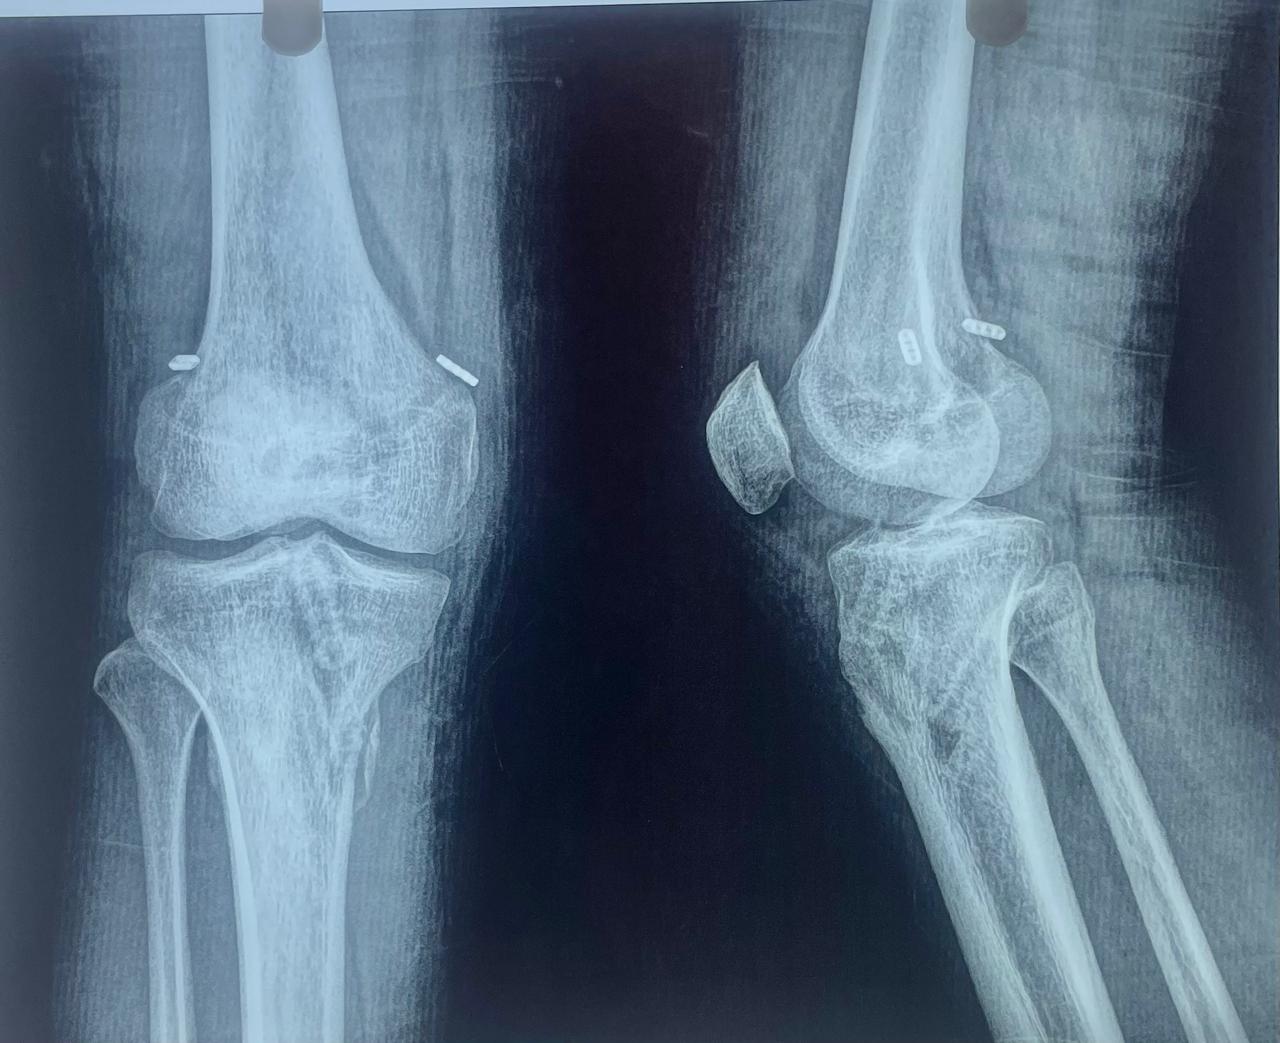

Images of Sports Injury:

Sport Injury